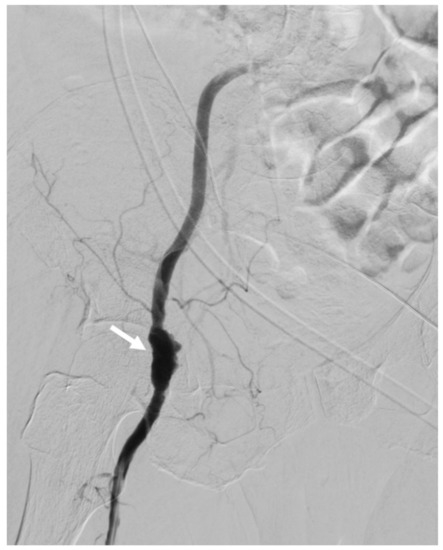

The patient was then admitted to the cardiovascular surgery ward with a scheduled operation. However, emergency angiography and surgery were arranged the following morning, due to the patient’s unstable hemodynamic status and hemorrhagic shock. Initial angiography revealed a right femoral artery, irregular-shape lesion, without contrast extravasation and suspected hematoma compression (Figure 3). The irregular shape of the patched vessel wall was due to infection.

Figure 3. Angiography revealed right femoral artery, irregular-shape lesion (arrow)with infection. No contrast extravasation due to hematoma compression effect.